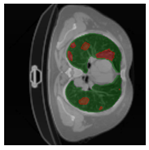

In Table 6, a comparison of the ground truth and prediction results of each model is presented in 2D, along with the 3D projection of each model. The visual analysis of the predictions provides additional insights into the performance of each model. The visualizations demonstrate that Attention UNet captures the intricate details of the lung construction more accurately, resulting in more precise segmentation of the infected areas compared to other models.

Table 6.

Comparison of ground truth and model prediction results using UNet, LinkNet, Attention UNet, UNet 3+, and TransUNet.